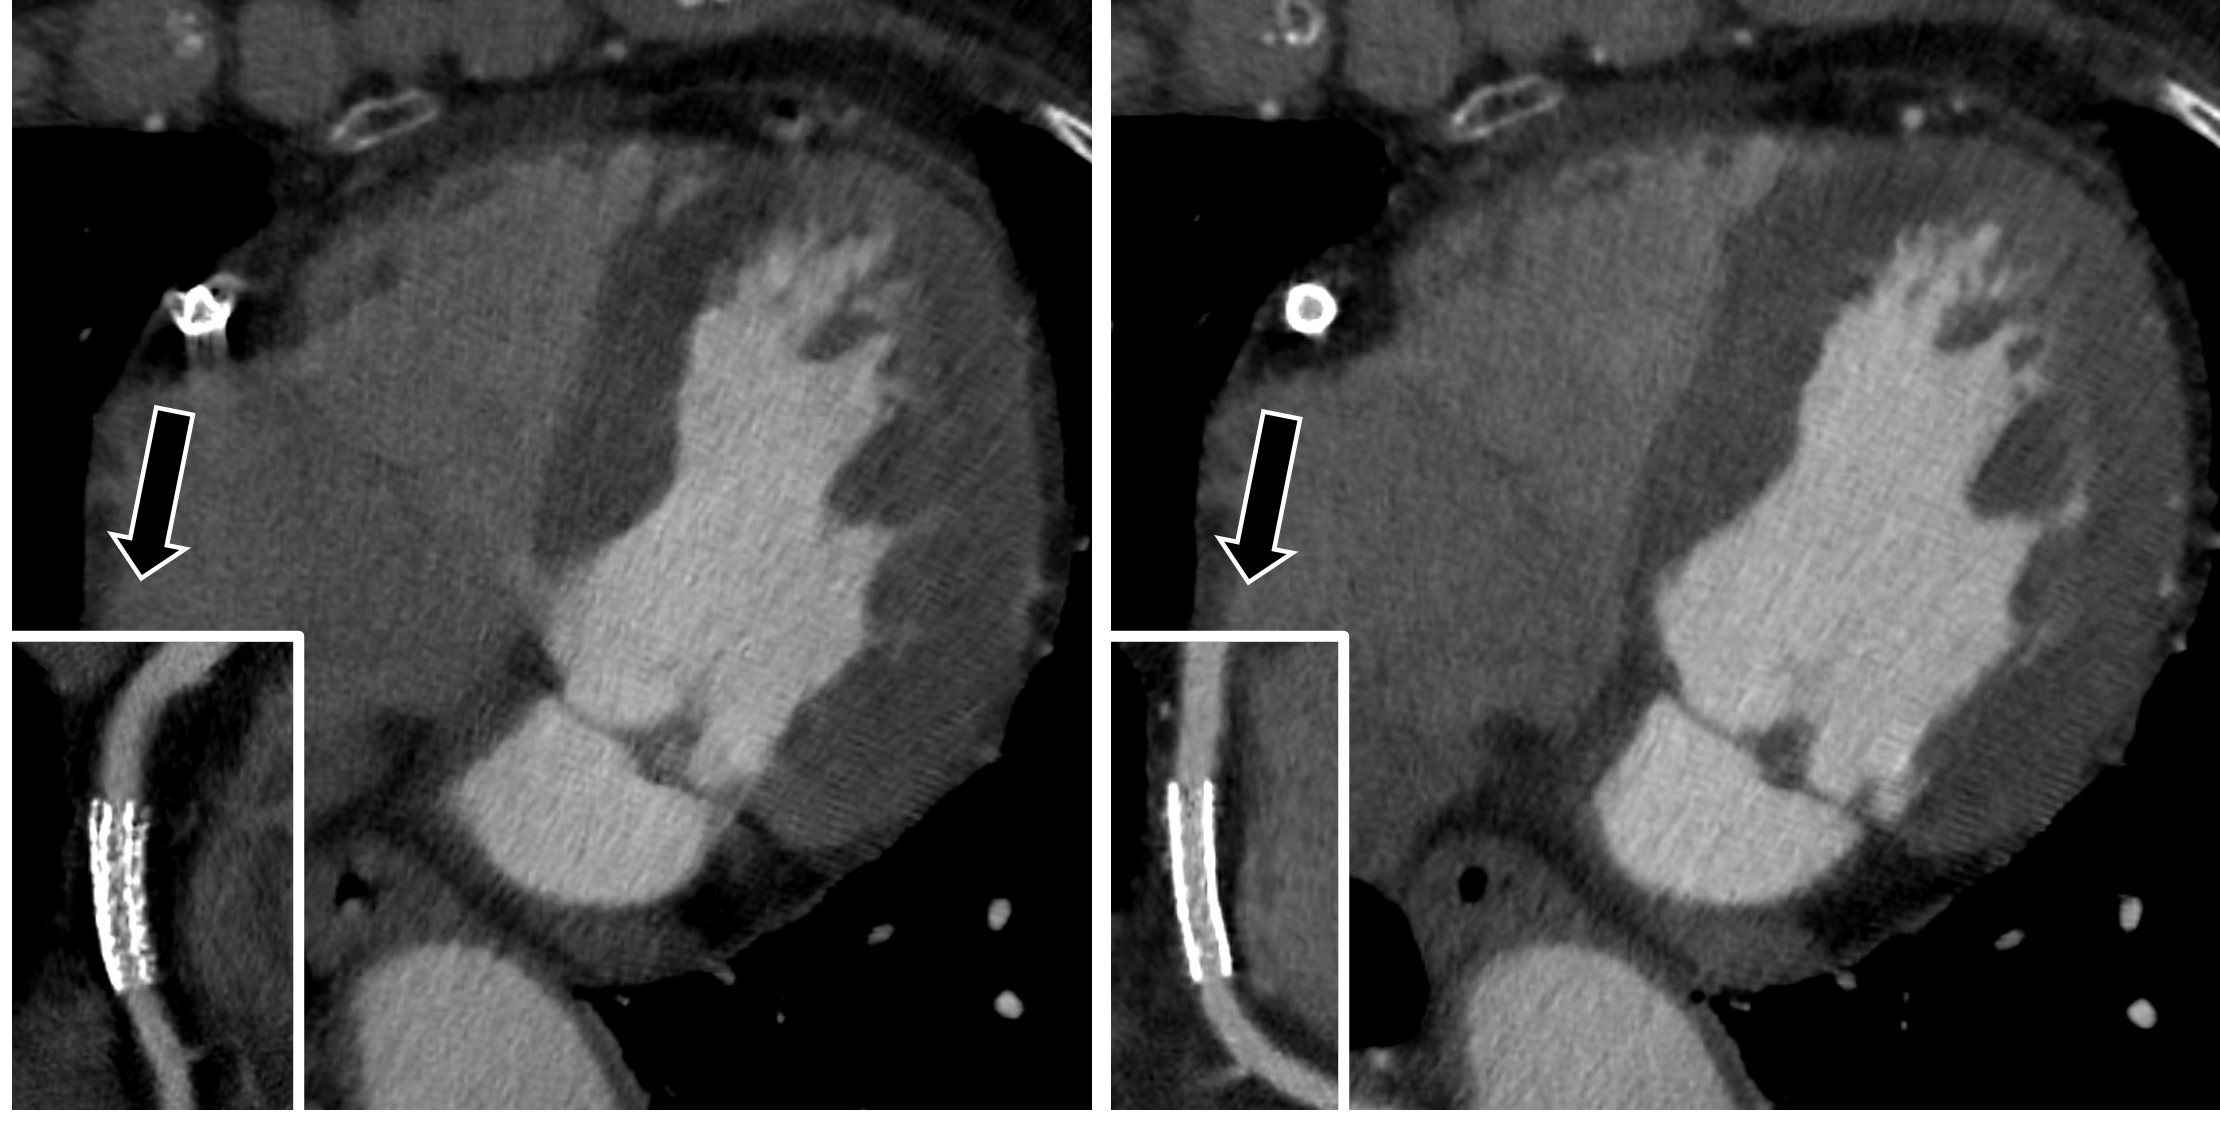

TAVI 後の CT は拡張期で人工弁が閉じている心位相を検索しますが、メタルアーチファクトやモーションアーチファクトの影響により血栓弁 (HALT) との鑑別が難しいことがあります。

しかし SSF2.0 を使用してからはほとんどアーチファクトのない画像を作成することが出来るようになり、とても診断がしやすくなりました。(Fig.4)

RevolutionCT_gifuheart05.jpg

Fig.4 HALT 症例における SSF2.0 の活用 (上段 SSF2.0 オフ / 下段 SSF2.0 オン)